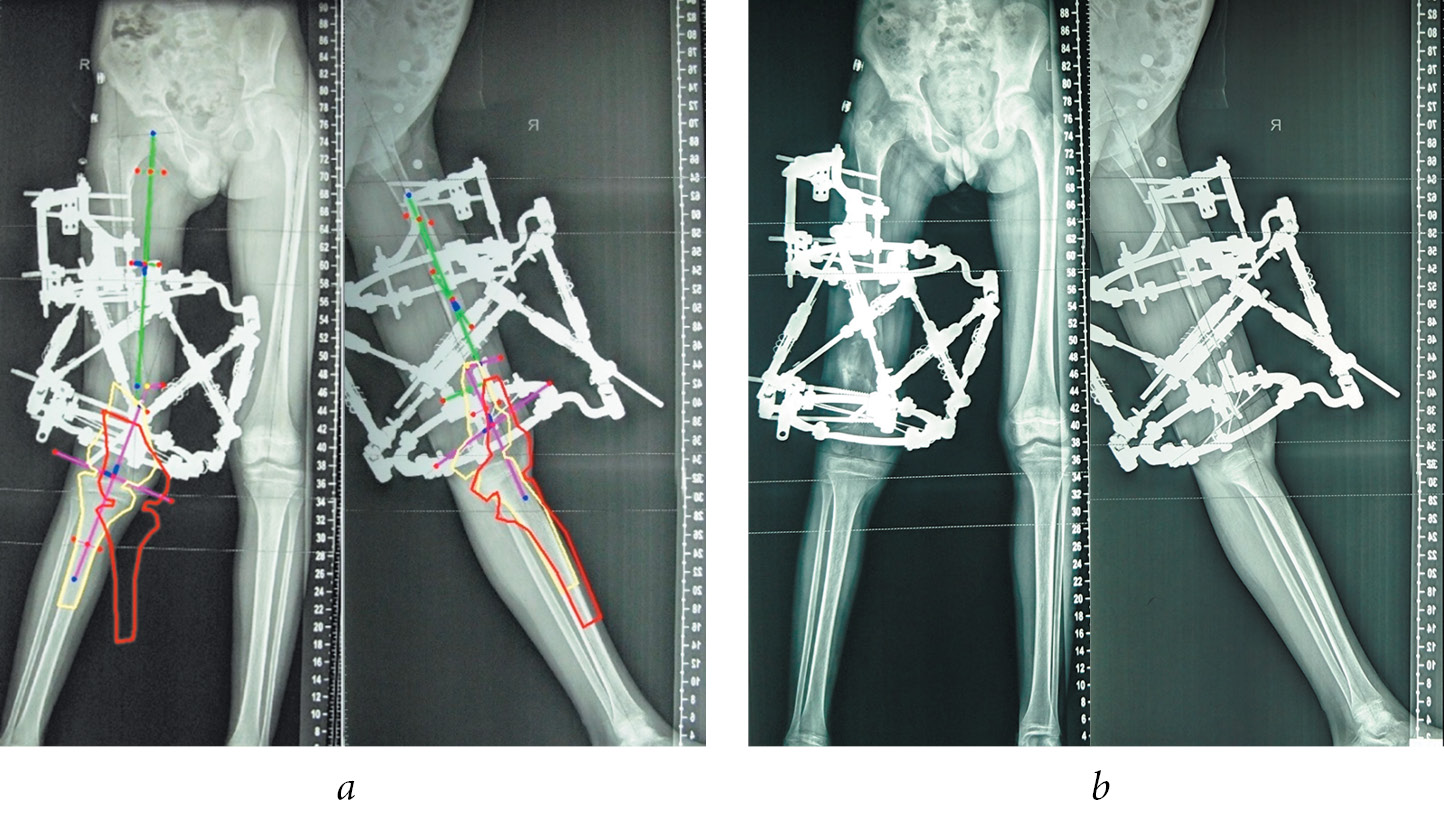

Клинический пример пациента из 1-й группы иллюстрируют рис. 1–3.

Рис. 1. Пациент Г., 12 лет, с последствиями гематогенного остеомиелита правого бедра, до лечения: а — внешний вид; б — панорамные рентгенограммы нижних конечностей, проведены механические оси проксимального и дистального отделов

Рис. 2. Пациент Г., 12 лет, с последствиями гематогенного остеомиелита правого бедра. Этап планирования и коррекции деформации: а — планирование коррекции деформации в компьютерной программе аппарата Орто-СУВ; б — после коррекции деформации